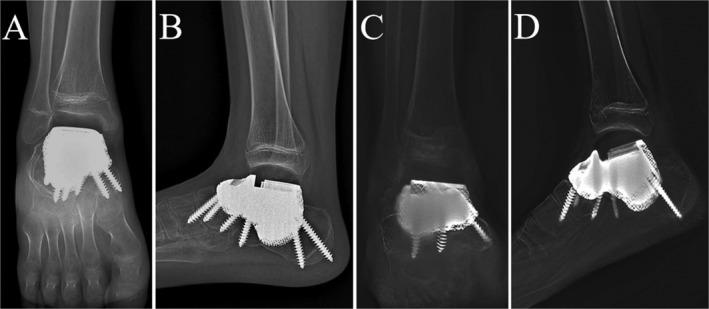

Here, we present the case of an 11-year-old adolescent patient diagnosed with Ewing's sarcoma of the talus, accompanied by suspected involvement of the calcaneus. Following a comprehensive evaluation, a 3D-printed talus-calcaneus prosthesis, which is composed of a ultrahigh-molecular weight polyethylene (UHMWPE) part and a titanium alloy part, was designed for talus and calcaneus reconstruction. In addition, a porous structure was designed to promote the integration of bone-prosthesis interface. The lesion was completely resected and the prosthesis was precisely installed. After 12 months follow-up, patients demonstrated favorable function results with the Musculoskeletal Tumor Society (MSTS) score was 27/30, and the American Orthopedic Foot and Ankle Society (AOFAS) score was 92/100. The range of motion for dorsiflexion, plantarflexion, inversion, and eversion of the right ankle joint was measured as 10° and 35°, 15°, and 10°, respectively. The postoperative radiograph showed a good position of the prosthesis. No narrowed joint space was observed. Tomosynthesis shimadzu metal artifact reduction technology (T-SMART) revealed that integration between bone and prosthesis was good.